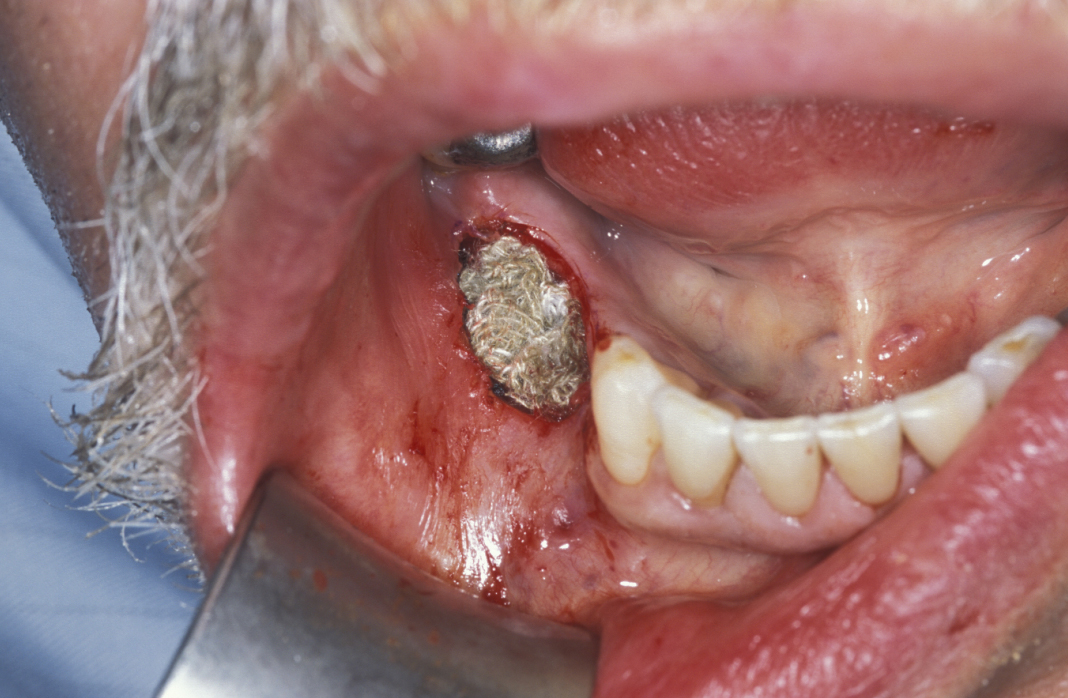

Limited resection represents a more aggressive form of removal of a cyst in that it will include the removal of bone in the vicinity of the cyst (a modified enucleation). It may also be a rim resection of the mandible (where a considerable portion of the mandibular bone is removed but a thin rim of the mandible is preserved to provide continuity of the bone). Treatment with Carnoy’s solution (a mixture of 60% alcohol, 30% chloroform and 10% concentrated acetic acid; applied locally directly after enucleation of a keratocyst) is popular with some surgeons. This is a way to reduce recurrence of keratocysts: the epithelial lining in keratocysts is very friable and therefore difficult to remove completely. Cryotherapy (local use of low temperature) may also have a role. A resection procedure with a reinforcing reconstruction plate is illustrated in Figures 10 to 15.

Figure 11: Approach to a large recurrent keratocyst that has grossly distorted the buccal cortex (outward facing cover of mandibular bone).